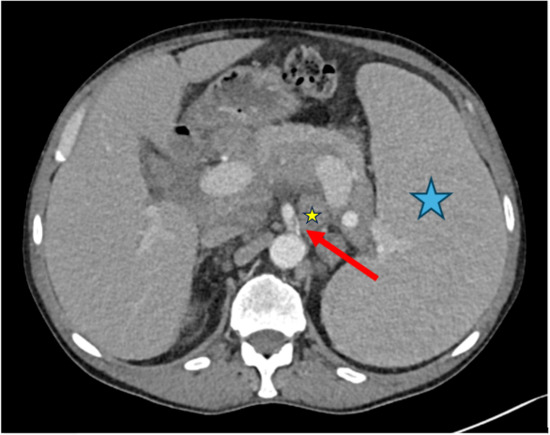

Figure 5.

Case 2, 60-year-old female. (a) Initial chest CT to clarify pulmonary embolism or COVID-19 findings showed pneumonic infiltrates of indeterminate appearance for COVID-19 (blue arrow) and revealed a large mediastinal mass (red arrow). (b) PET/CT demonstrated mild FDG-uptake, making the diagnosis of thymoma more likely than lymphoma.